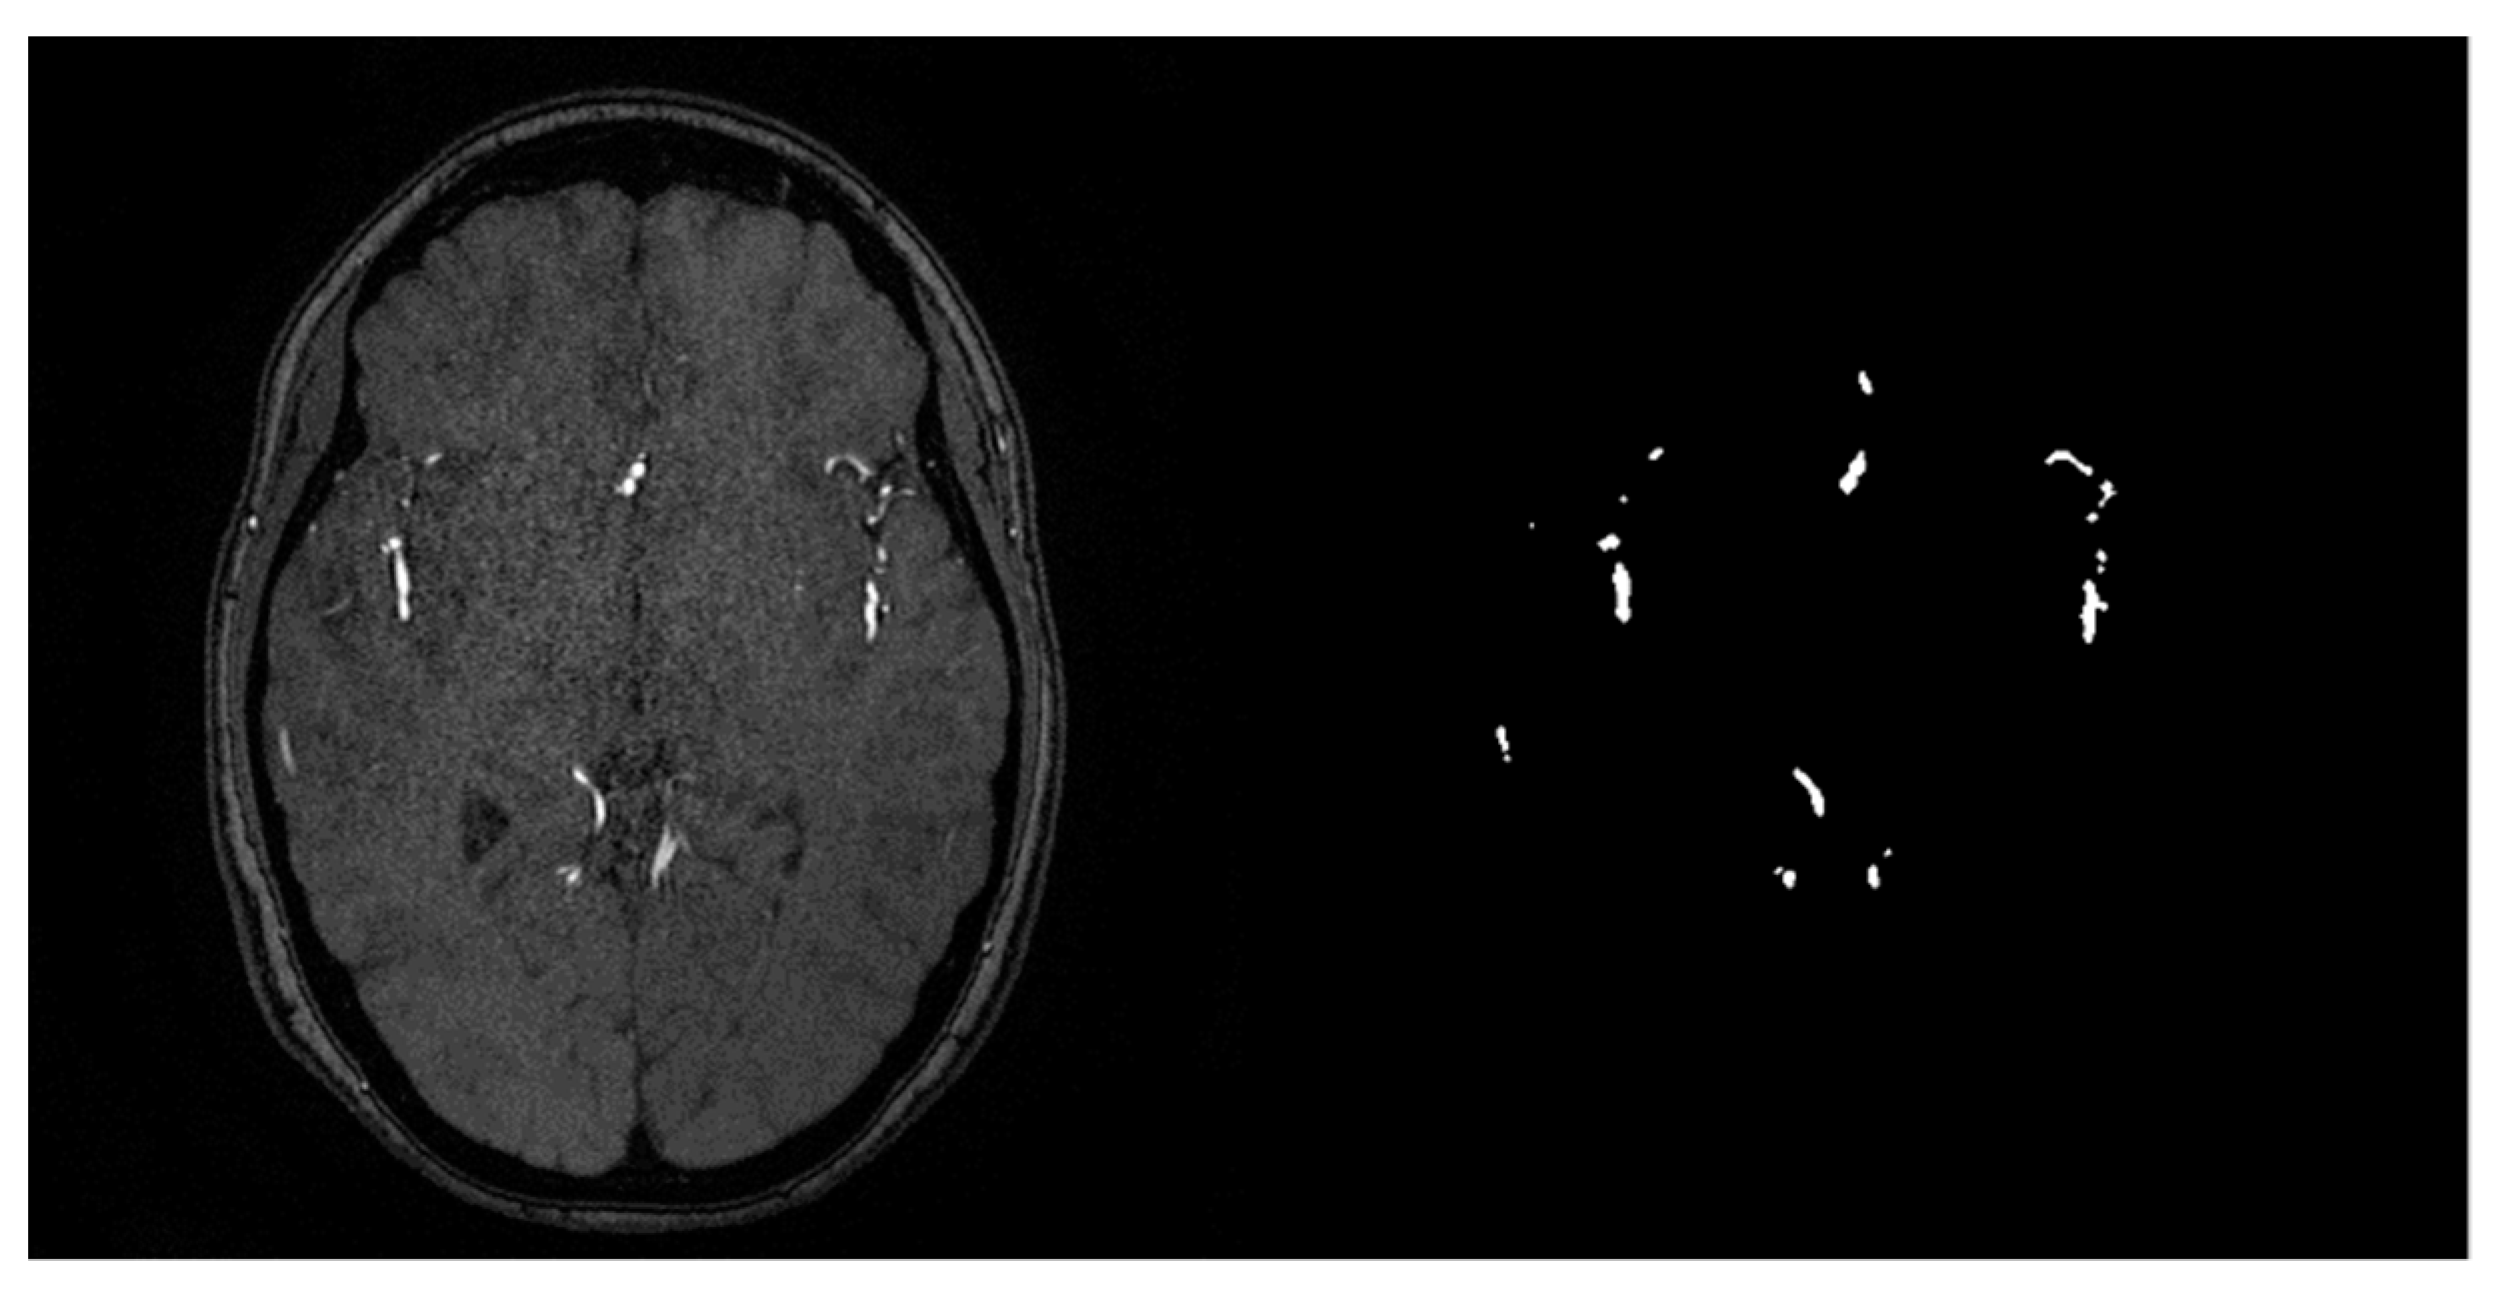

- MRA Images